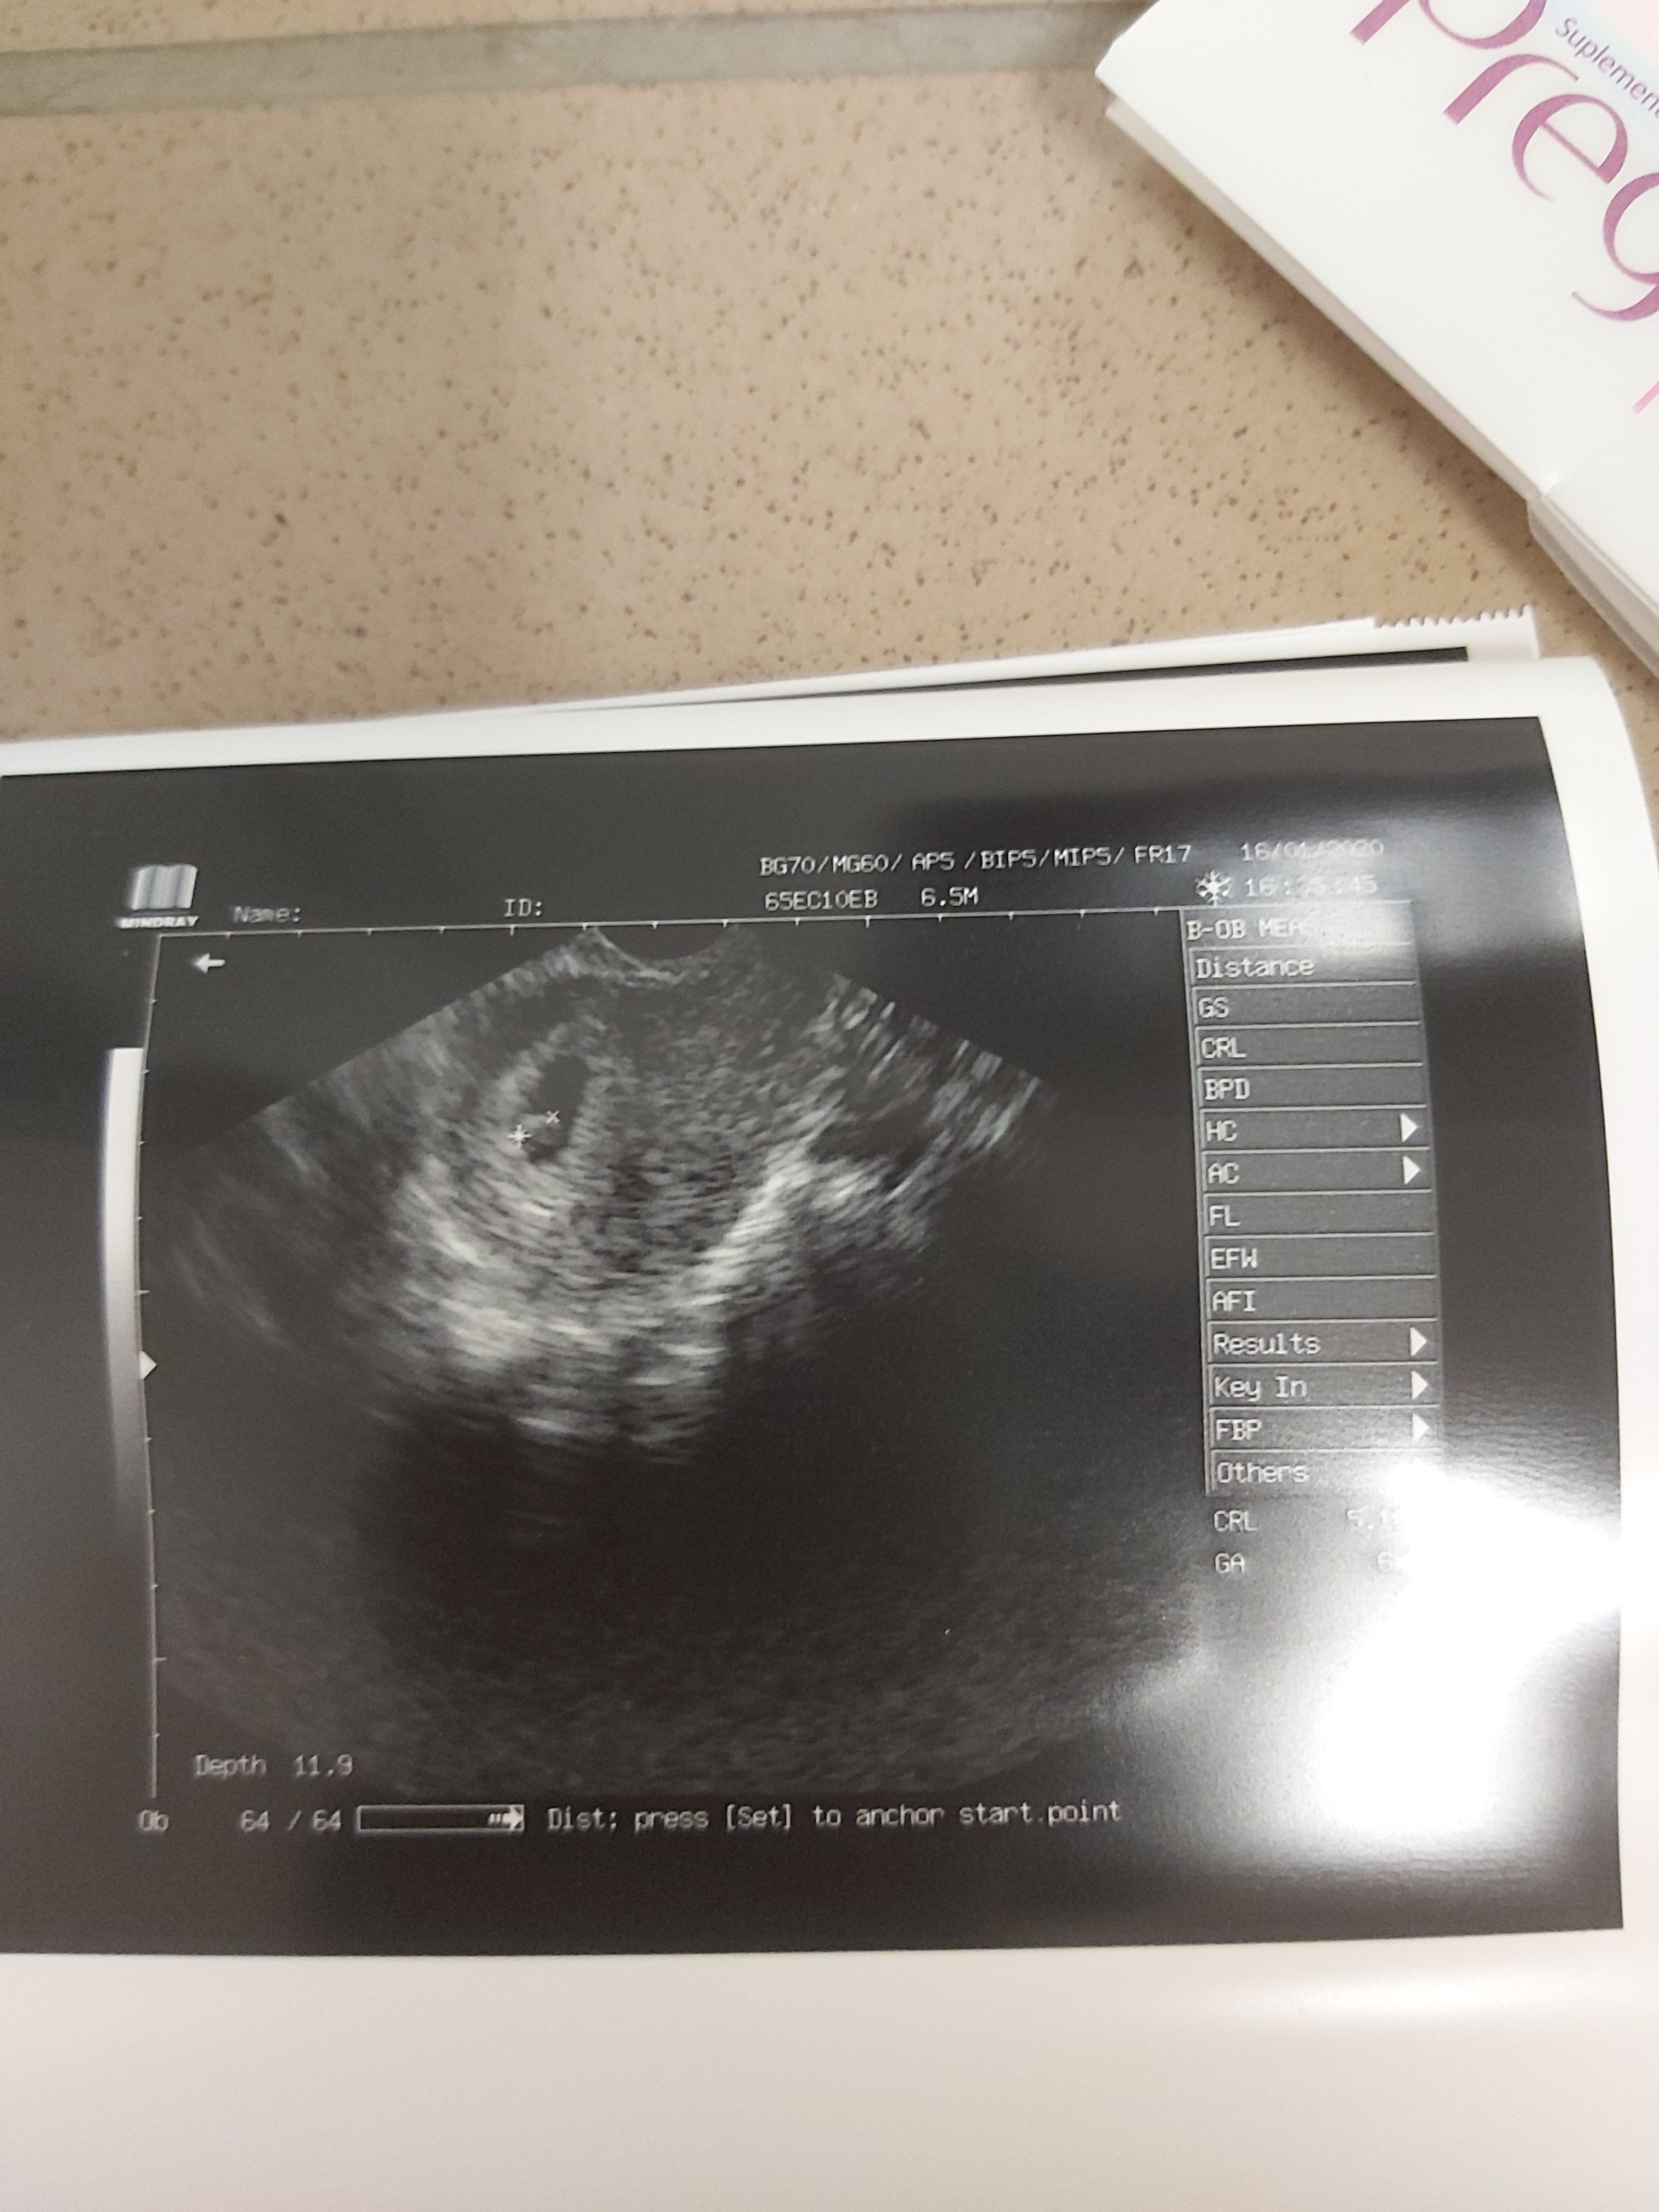

21.01.20r stał się CUD!! Po krwiaku nie ma śladu!

Kropka ma 0,67cm, 6t4d, serducho bije jak dzwon i wszystko w jak najlepszym porządku! <3

Przypomnę tylko, że tydzień wcześniej Kropka miała 3mm i też już było serduszko ale i ogromny krwiak , który dawał marne szanse na utrzymanie ciąży.